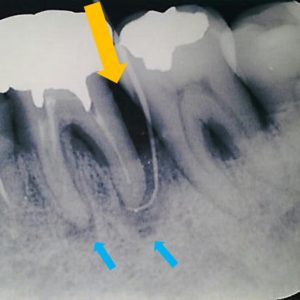

下は術前写真です。

オレンジ矢印から9mmの歯周ポケットがあり、また青矢印部分に根尖病巣が認められます。